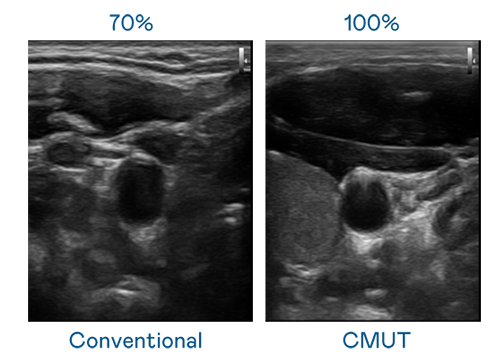

CMUT 技术是一种用电容式微机电元件来产生超音波讯号的技术。与传统 PZT 压电式技术相比,CMUT 频宽增加 30%,更宽频的超音波讯号让影像解析度大幅提升,是实现高影像品质医疗超音波扫描、促进精准医疗发展的关键技术。

大频宽带来超清晰影像

超音波影像的解析度高低,首先取决于探头能发出的讯号频宽。z6mg人生就是博 CMUT 可提供高清晰的超音波讯号,提供高频宽、高灵敏度、影像纹理细节更高的超音波影像,协助医护人员缩短影像判读时间及利用精准的医疗影像进行诊断。